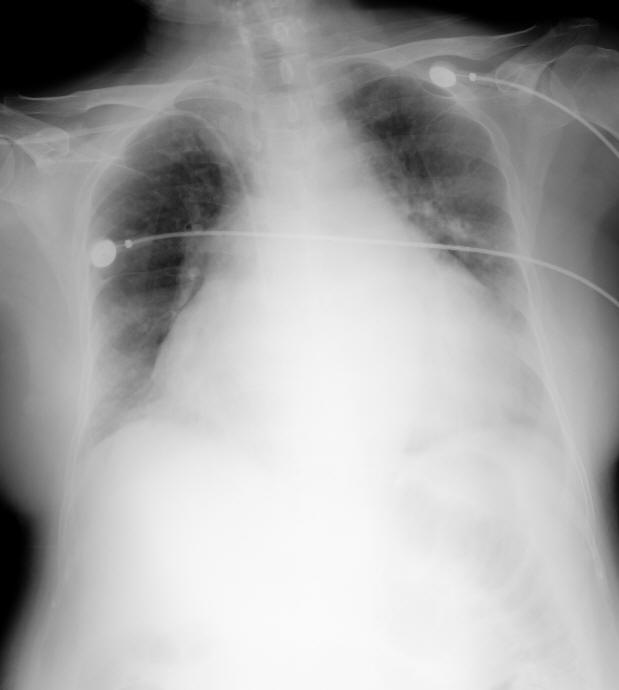

以下是引用前行在2008-4-27 19:28:00的发言:[br]慢性心功能不全

以下是引用dyqct在2008-4-27 19:22:00的发言:[br]心脏呈普大型,请结合临床听诊、心电图除外心衰。